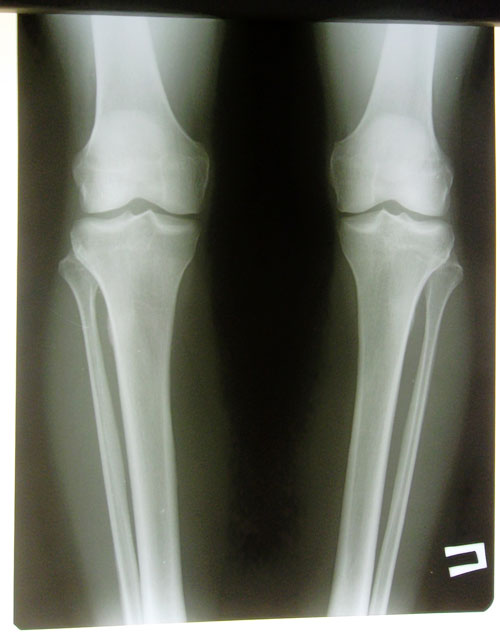

Дата операции 14.11.2013г.

Дата снятия аппаратов 24.03.2014г.

Срок лечения 130 дней.